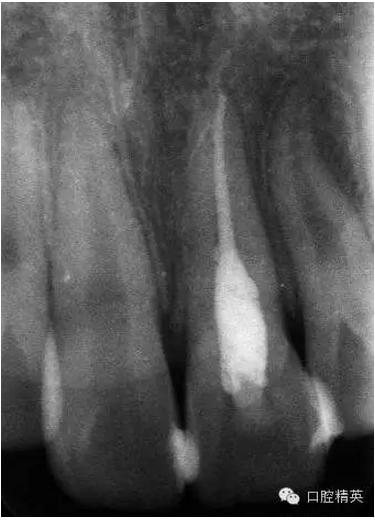

x線(xiàn)檢查:21牙槽窩空虛,窩內(nèi)未見(jiàn)其他遺留物。

圖3.患者21根尖片,牙槽窩空虛,無(wú)變形。

圖18.復(fù)位臨時(shí)固定后的x線(xiàn)根尖片。患者牙根與牙槽窩吻合。

圖23.樹(shù)脂+牙弓夾板固定完成后的x線(xiàn)片影像

圖5.拆除樹(shù)脂夾板前的x線(xiàn)根尖片影像,21根尖出現(xiàn)少許吸收。大家擔(dān)心的情況出現(xiàn)了。